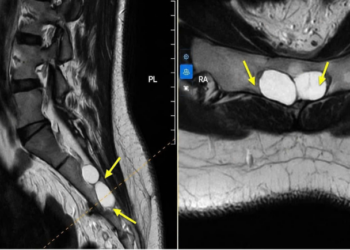

Chẩn đoán

Bác sĩ sẽ hỏi bệnh và thăm khám để tầm soát nguyên nhân gây đau khớp, cần thiết sẽ chỉ định chụp Xquang khớp.

Nếu cần, bác sĩ có thể yêu cầu bạn xét nghiệm máu để kiểm tra các vấn đề rối loạn tự miễn dịch hoặc xét nghiệm tốc độ máu lắng để đánh giá mức độ viêm trong cơ thể.